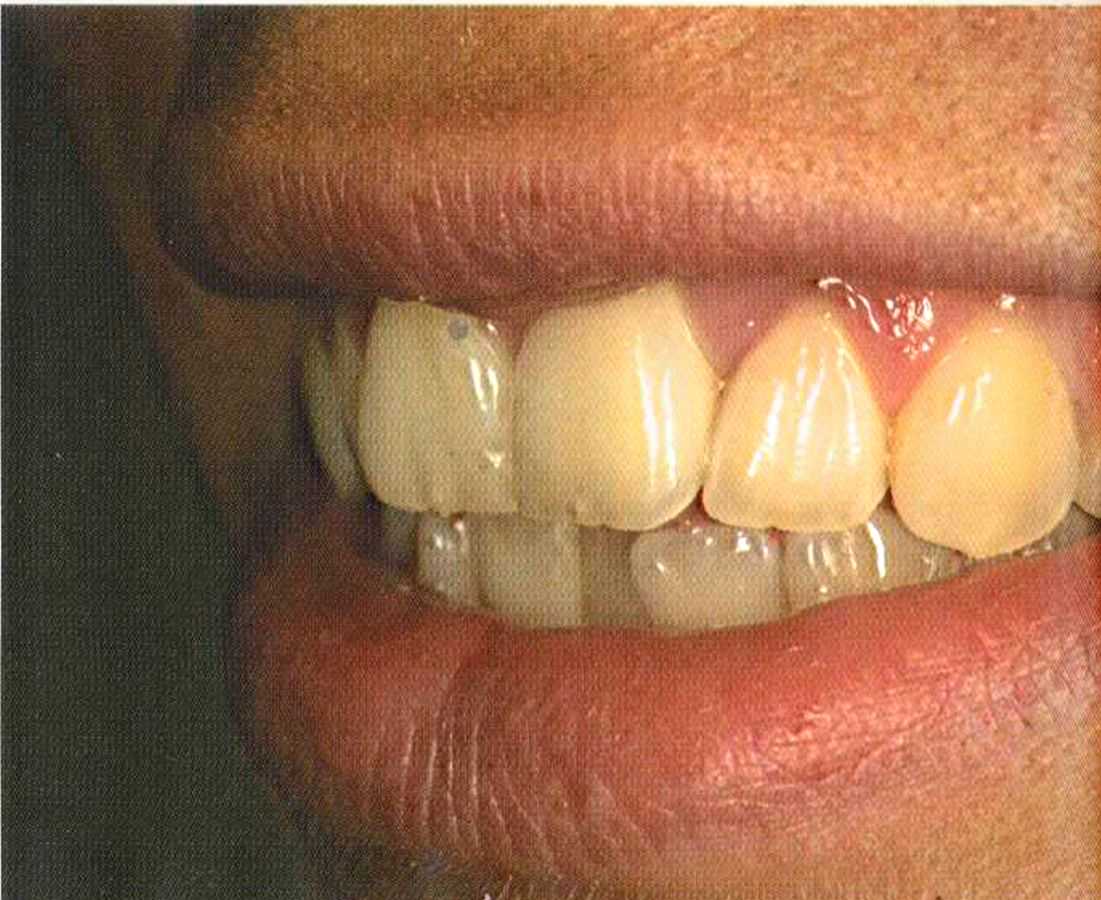

Первое лечение проходию много лет назад у другого доктора. Со временем ос те пи / ка уху дин ьась, особенно в пришеечной области. Этот пациент хотел новые коронки в области 12 и 22, по сомневсься, нас кол ько хорошо они будут выглядеть.

Фото внизу.

Результат с использованием In-Ceram развеял все сомнения, и решение об изготовлении коронки на другой боковой резец не заставило себя долго ждать.

После того как мы определит цвет зуба, решено быо сначсьа изготовить одну коронку.